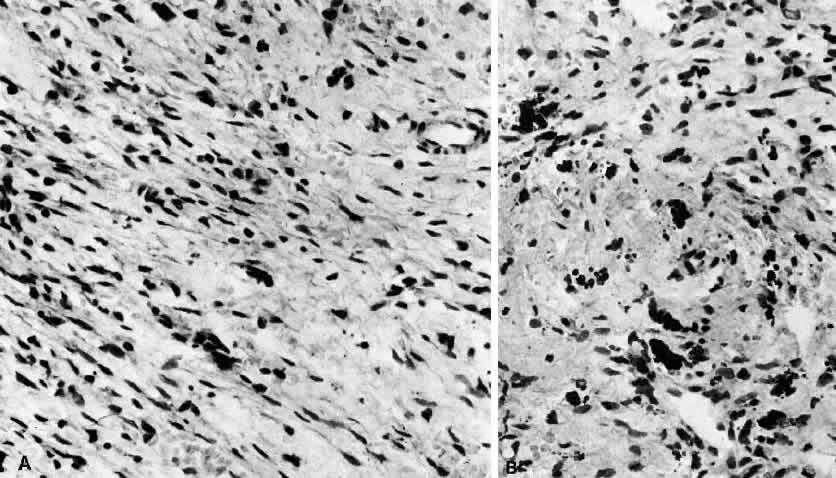

In general, idiopathic orbital inflammation is polymorphic (Figs. 5 AND 6).3,6,7,33,87,88 The cellular response seen in this disease consists of lymphocytes, plasma cells, macrophages, histiocytes, occasional neutrophils and eosinophils, epithelioid cells, and fibroblasts. These are present in varying numbers, depending on the chronicity of the inflammatory process. Intranuclear Dutcher bodies and intracytoplasmic Russell bodies may be present within many of the plasma cells since they actively participate in the inflammatory response. Children tend to have a significant number of eosinophils in their biopsy specimen. Lipogranulomatous inflammation with fat necrosis may also be present. However, the presence of noncaseating granulomas is relatively uncommon.89 This is often associated with foreign body giant cells that are responding to the release of lipid. Perivascular lymphocytic cuffing and capillary proliferation are quite common.3 Occasionally, lymphoid follicles may also be seen.

Fig. 6. Histopathologic sections demonstrating the various pathologic findings associated with idiopathic orbital inflammation. Most commonly these include lymphoid follicles, granulomas, collagen deposition, and a diffuse mixed inflammatory cell infiltrate. The normal tissue architecture is frequently disrupted by these changes. A. Many lymphoid follicles are scattered throughout orbital tissue (H&E, × 63). B. Cells of follicular center are lighter and larger than mantle of mature lymphocytes that surround the germinal zone (H&E, ×160). C. Lacrimal gland elements have undergone atrophy in advanced example of idiopathic dacryoadenitis. Fibrosis and lymphocytes have replaced a considerable amount of gland parenchyma (H&E, ×94). D. Myositis in which lymphocytes are loosely aggregated below center and infiltrate between extraocular muscle fibers (H&E, ×160). E. Cuffing of small vessels by mature lymphocytes. Note loose edematous interstitium between disrupted muscle fibers (H&E, ×240). F. Progressive fibrosis of retrobulbar fat (H&E, ×25).

Fig. 7. Fasciitis. A. “Pseudosarcomatous” reactive inflammatory condition is composed predominantly of a loose arrangement of fibroblasts with scattered chronic inflammatory cells (H&E, ×240). B. Conspicuous hemosiderin-laden macrophages are seen in center of photomicrograph. The presence of abundant numbers of capillaries in the inflammatory tissue results in hemorrhage and the presence of blood breakdown products (H&E, ×240).